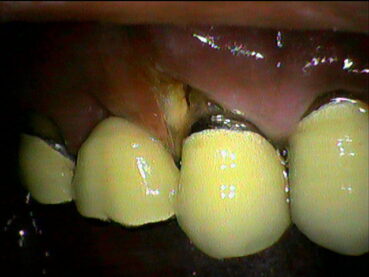

進行すると「歯がぐらつく」「口臭が強くなる」「噛むと痛い」といった症状が現れ、最終的には歯が抜けてしまうこともあります。

歯周病の進行具合にあわせて、治療の内容も変わります。東松山のくるみ歯科医院では、できるだけ歯を残すためのステップを踏んでいく形です。